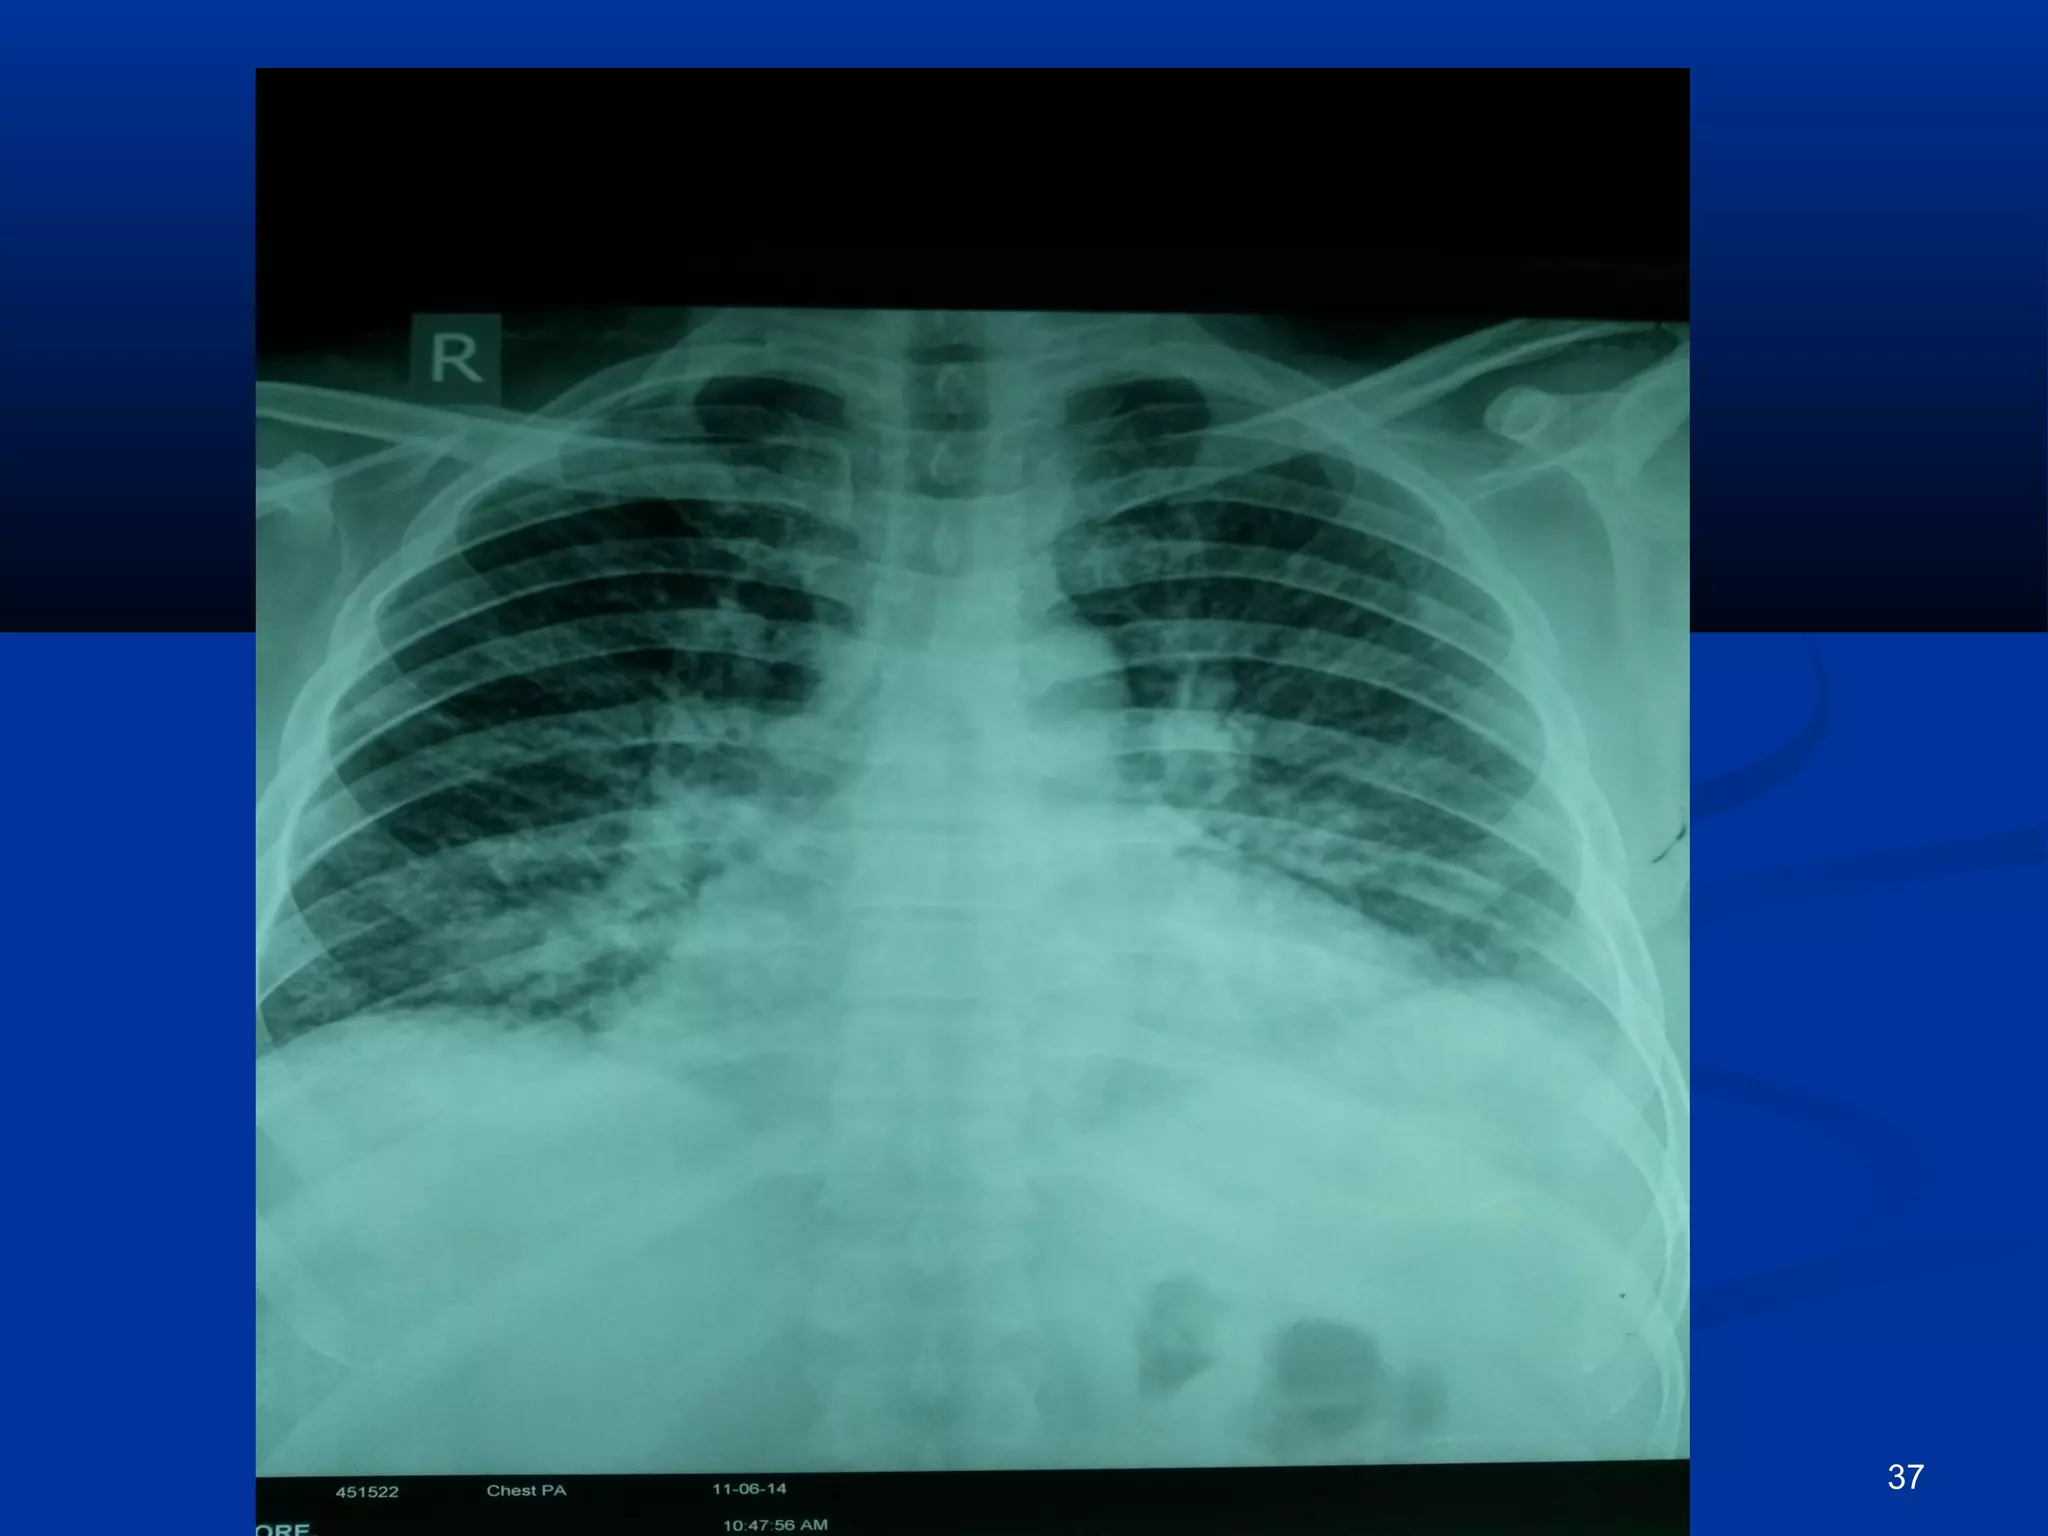

EEcchhooccaarrddiiooggrraapphhyy

42

 CCTT.. bbrraaiinn,, EECCHHOO,, aanndd DDoopppplleerr II sshhoowweedd yyoouu.. 50

• TTrraannsstthhoorraacciicc ((TTTTEE)) aanndd ttrraannssooeessoopphhaaggeeaall

((TTEEEE))

• ffuunnddaammeennttaall iimmppoorrttaannccee iinn ddiiaaggnnoossiiss,,

mmaannaaggeemmeenntt,, aanndd ffoollllooww--uupp

• SShhoouulldd bbee ppeerrffoorrmmeedd aass ssoooonn aass tthhee IIEE iiss

ssuussppeecctteedd

• SSeennssiittiivviittyy ooff TTEEEE iiss bbiiggggeerr tthhaann TTTTEE ((vvss 900--

110000%% vvss.. 4400--6633%% ))

• TTEEEE iiss ffiirrsstt cchhooiiccee ttoo ffiinndd IIEE ccoommpplliiccaattiioonnss

EEcchhooccaarrddiiooggrraapphhiicc ffiinnddiinnggss iinn IIEE

• VVeeggeettaattiioonn

• AAbbsscceessss

• PPsseeuuddooaanneeuurryyssmm

• PPeerrffoorraattiioonn

• FFiissttuullaa

• VVaallvvee aanneeuurryyssmm

• DDiisshheennccee ooff pprroosstthheettiicc vvaallvvee